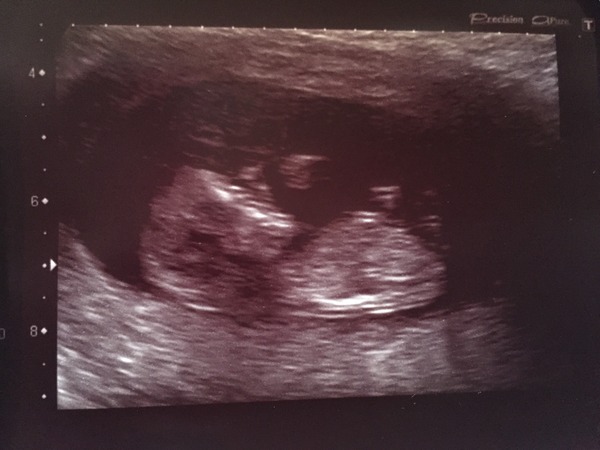

I had a fab scan. Wriggly little baby and strong heartbeat too. Dp couldn't see the nub (nor me but that's no surprise) but I'm guessing boy.

Aww, great scan pic Fluffeh :-D All good here too, hurrah! Think bubs was snoozing, and seemed pretty unimpressed when we tried getting him/her to move into a better position, but got there in the end. Measuring bang on for dates. Lovely sonographer gave us 6 pics instead of the 3 they're meant to so that was great too.